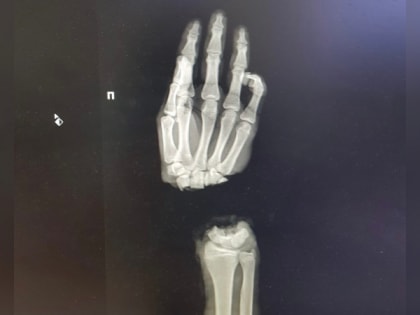

16 - летнему юноше из Владимирской области врачи сумели пришить отрубленную руку

16 - летнему юноше из Владимирской области врачи сумели пришить отрубленную руку.

16-летний юноша из города Коврова колол дрова и отрубил себе кисть правой руки.

Медики из ПИМУ спасли кисть 16-летнего ковровчанина. Об этом рассказали в группе «ВКонтакте» Приволжского медицинского университета .